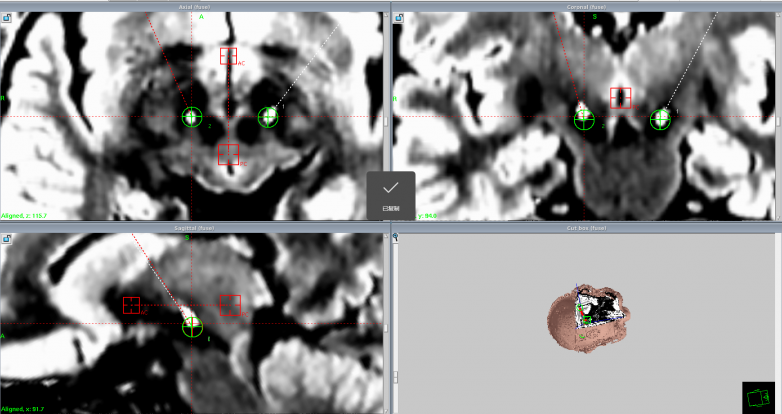

計偉主任帶領手術團隊,以精湛的技藝和嚴謹的態度投入到手術操作中。他們借助先進的影像導航技術,精準定位核團靶點,每一個操作都小心翼翼、精準無誤。在植入設備的過程中,手術團隊密切配合,精細操作,確保電極準確無誤地植入到預定位置。整個手術過程緊張而有序,手術最終順利完成。術后患者各項生命體征平穩,神志清醒,肢體活動良好,顱腦CT及各項檢查均未見異常,手術取得了圓滿成功。